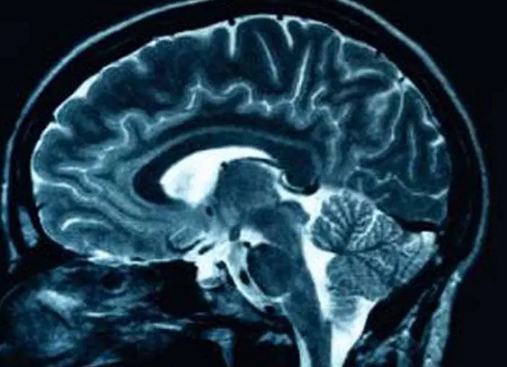

To understand the CC’s genetics, the team built an AI tool called SMACC (Segment, Measure, and AutoQC the mid-sagittal Corpus Callosum). Think of it as a digital archaeologist for brain scans: it uses MRI images to precisely outline the CC, measure its thickness and shape, and even detect subtle regional differences.

Using SMACC, they analyzed brain scans from two large public datasets—the UK Biobank, which includes middle-aged and older adults, and the Adolescent Brain Cognitive Development (ABCD) study, which tracks the development of children and teens. Together, these provided a rare chance to see how genes influencing the CC may act across a lifetime—from a 10-year-old’s developing brain to an adult’s slowly thinning one.